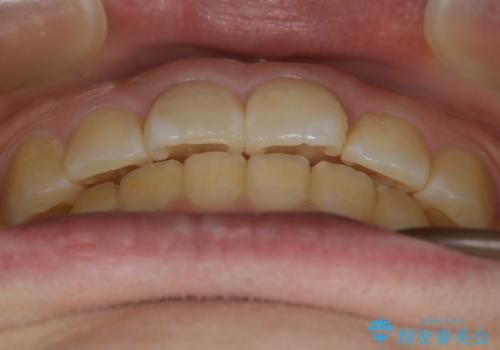

【非抜歯】ガタつきと歯軸を正して長持ちする歯へ

- 歯のガタつきと噛み合わせの改善を主訴に来院されました。

非抜歯で、少量の奥歯の移動と歯列の拡大・IPRを駆使して主訴を改善するための治療計画を立案しました。